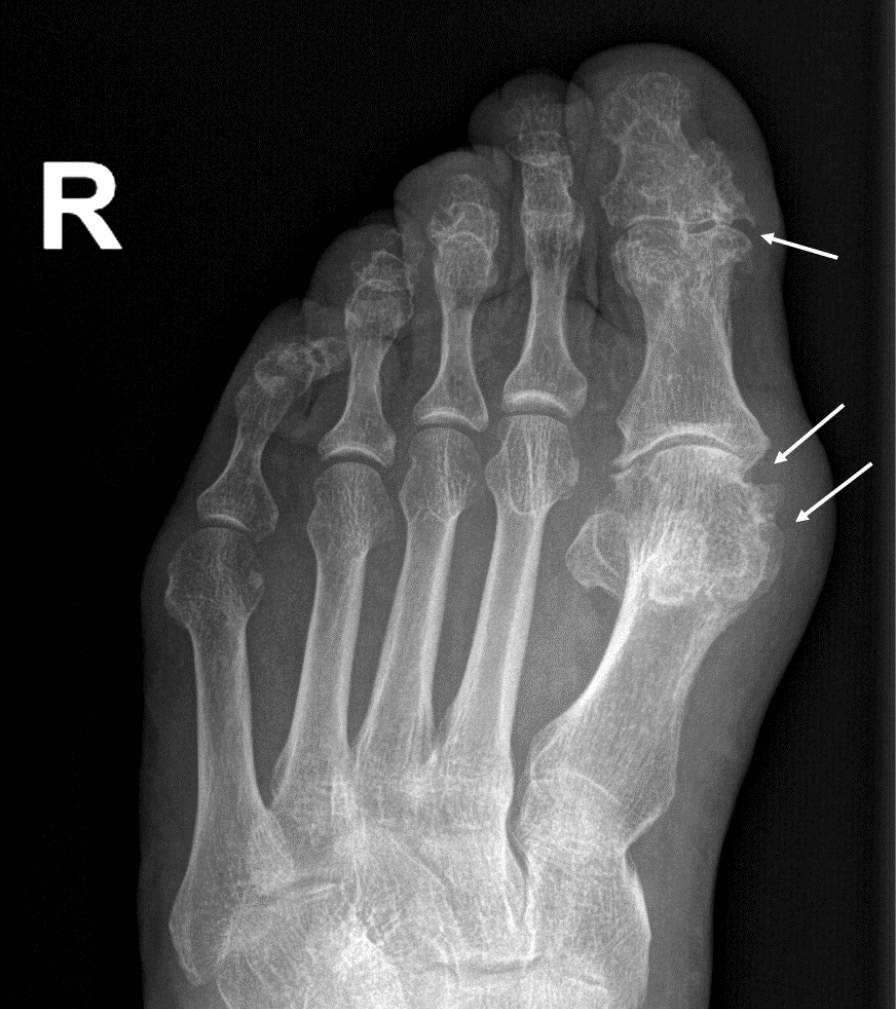

При компьютерной томографии органов грудной клетки данных за «свежие» очаговые и инфильтративные изменения не получено. Увеличения лимфатических узлов подмышечных областей, средостения, корней легких не выявлено. Отмечался усиленный грудной кифоз, обызвествление передней продольной связки, на всем уровне исследования определялись передне-боковые спондилофиты, а также анкилоз большинства реберно-поперечных суставов. По данным рентгенографии кистей (рис. 1, 2) и стоп (рис. 3, 4) диагностированы признаки эрозивного артрита, анкилоз суставов запястья. По данным МРТ крестцово-подвздошных суставов (КПС) определялся неравномерный анкилоз КПС, хрящи по суставным поверхностям неравномерной толщины, примерно на половине протяжении сустава отсутствуют, «суставной промежуток» облитерирован. Неравномерность и нечеткость контура суставных поверхностей за счет множества краевых эрозий справа, единичных – слева, с наличием остеокластоза, в нижнем отделе слева по смежным отделам определяются участки трабекулярного отека, данная находка клинически интерпретирована как двусторонний активный сакроилиит (рис. 5, 6).

Рис. 3. Рентгенограмма правой стопы в прямой проекции. Краевые эрозии суставных поверхностей первого плюсне-фалангового сустава и межфалангового сустава I пальца (стрелки), сужение суставных щелей. Вальгусная деформация I пальца стопы

Рис. 4. Рентгенограмма левой стопы в прямой проекции. Краевые эрозии суставных поверхностей первого плюсне-фалангового сустава (стрелки), сужение суставной щели. Вальгусная деформация I пальца стопы